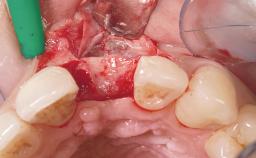

Bone Augmentation No

Augmentation Materials -

Soft Tissue Grafting None

Placement Protocol Immediate implant placement

Socket Integrity Damage to one or more bone walls

Bone Volume Damage to one or more socket walls